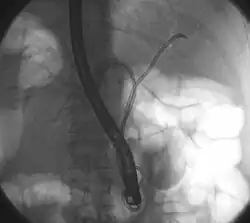

Das zuerst durchgeführte bildgebende Verfahren ist in der Regel die Ultraschalluntersuchung des Bauches. Sie eignet sich vor allem zur Erkennung gutartiger Ursachen der Symptome (wie z. B. Gallensteine) und zur Darstellung erweiterter Gallenwege bei der Cholestase. Auch Tumoren bzw. Metastasen im Lebergewebe sind im Ultraschall häufig zu erkennen. Der Klatskintumor kann unter Umständen so erkannt werden. Generell eignet sich Ultraschall aber nicht zur sicheren Darstellung des Tumors und zur Ausbreitungsbestimmung. Die Untersuchung der Wahl dafür ist die Computertomographie (CT) mit Kontrastmittel von Brustkorb und Bauch. Hier kann die Lage und Ausbreitung des Tumors bestimmt werden und dazu, ob bereits Lymphknoten befallen sind und ob der Tumor benachbarte Blutgefäße wie die Pfortader ummauert oder in sie einwächst. Zur Planung der Operation können hier auch die Lebergefäße dargestellt und die Größe der Lebersegmente und das verbleibende Lebervolumen berechnet werden. Die Untersuchung ist ein wichtiger Teil der Stadienbestimmung. Ergänzend kann eine Magnetresonanztomographie (MRT) mit Kontrastmittel zur besseren Darstellung der Gallenwege und des Tumors durchgeführt werden. Die sonst bei Erkrankungen der Gallenwege häufig eingesetzte ERCP, eine invasive Methode zur Darstellung der Gallenwege mit der Möglichkeit zur Intervention, wird bei Verdacht auf Klatskintumoren zurückhaltend eingesetzt, da hier das Risiko für eine bakterielle Cholangitis deutlich erhöht ist. Alternativ bietet sich die nicht-invasive MRCP an. Die ERCP kommt vor allem bei unklaren Fällen zum Einsatz, um mit einer kleinen Bürste Zellen aus dem verdächtigen Gangabschnitt zu gewinnen (Biopsie). Diese können bei der Diagnose den Weg weisen. Die ERCP ermöglicht auch therapeutisch die Einlage von Stents zur Entlastung der Cholestase.[3][8][13]

Für eine eventuelle Zweitlinientherapie gibt es keinen etablierten Standard. Häufig werden Fluorpyrimidin-basierte Therapieschemata verwendet.[3] Die Verengung oder der Verschluss der Gallenwege mit daraus folgendem Gallestau ist, wie beschrieben, ein häufiges Problem, da sie zu Gelbsucht mit Juckreiz und bakteriellen Infektionen führen kann. Hier können Stents aus Metall oder Plastik in die Engstellen gelegt werden, um so die Galle abfließen zu lassen. In diesem Rahmen hat ein weiteres lokales Therapieverfahren vermehrte Aufmerksamkeit bekommen: die photodynamische Therapie (PDT). Dabei wird ein Photosensibilisator in den Körper eingebracht, der sich in den Tumorzellen anreichert. Bestrahlung mit Licht in einer bestimmten Wellenlänge führt zur Freisetzung von Sauerstoffradikalen, die die Tumorzelle schädigen. In Kombination mit der photodynamischen Therapie bleiben eingelegte Stents länger offen.[24] Ein weiteres Feld, auf dem geforscht wird, ist die Anwendung von molekular gezielten Therapien und von Immuntherapien. Für molekular gezielte Therapien wird der Tumor genetisch untersucht, um herauszufinden, welche Genveränderung das Wachstum der Krebszellen antreibt. Für viele solcher Gene gibt es mittlerweile Medikamente (monoklonale Antikörper oder Tyrosinkinase-Inhibitoren), die gezielt die „Achillesferse“ angreifen und das Wachstum behindern. Solche Therapien sind bereits bei einigen Tumorerkrankungen etabliert, aber bei Cholangiokarzinomen bisher erst in den Anfängen (Stand 2018).[23]